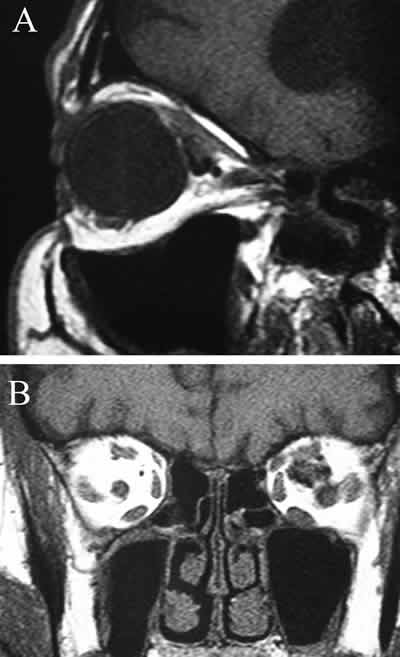

Aporta un estudio de RMN de órbitas en cortes axial, coronal y sagital con inyección de Gadolinio, objetivándose una masa intracónica en el cuadrante nasal y superior de la órbita izquierda en íntimo contacto con el nervio óptico y los músculos oblicuo mayor, recto superior y recto interno en sus 2/3 anteriores, con diámetros transverso, antero-posterior y vertical de 1,7x1,3x1,2 cm, considerándose el hemangioma intracónico la principal posibilidad diagnóstica (fig. 4).

Fig. 4: A: RMN sagital SE T1 con gadolinio (Gd-DPTA). B: RNM coronal SE T1. Masa intracónica en el cuadrante nasal y superior de la órbita izquierda relacionada con nervio óptico y músculos oblicuo mayor, recto superior y recto interno, de 1,7x1,3x1,2 cm.